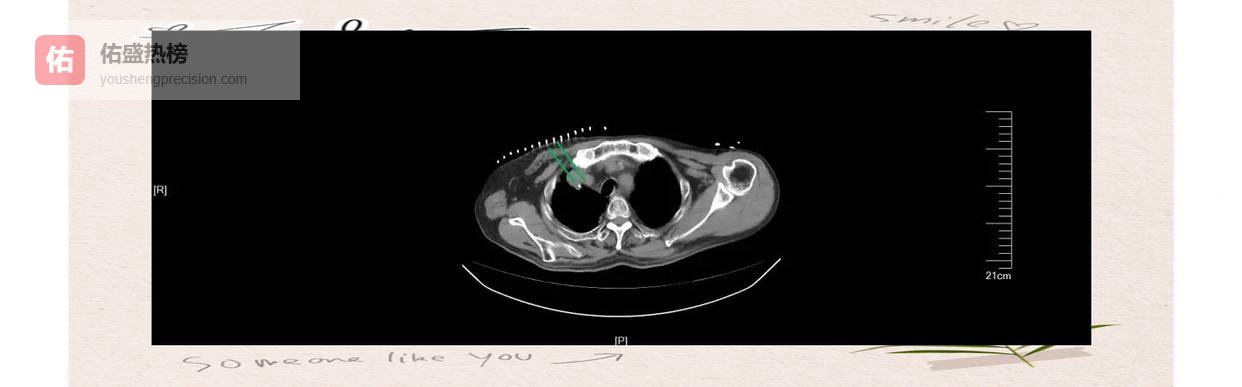

2.1 ► 术前精准“定位” 借助CT/MRI融合靶向定位,医生能在术前把病灶“放大”在三维模板上,确保每一粒种子都落在“癌巢”正中央。

2.2 ► 术中实时“导航” 超声或CT引导下,粒子被一根细针“投篮”式植入,实时监测阻力与深度,避免穿透血管或重要脏器。